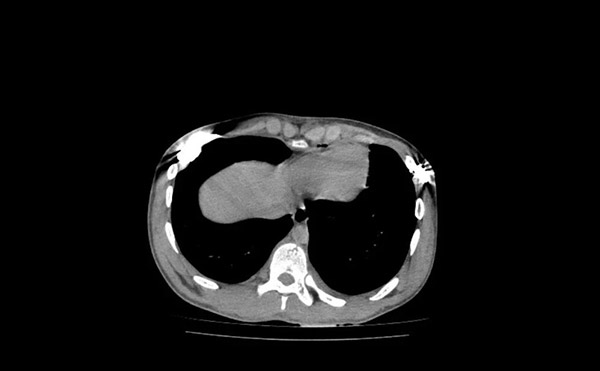

手术后